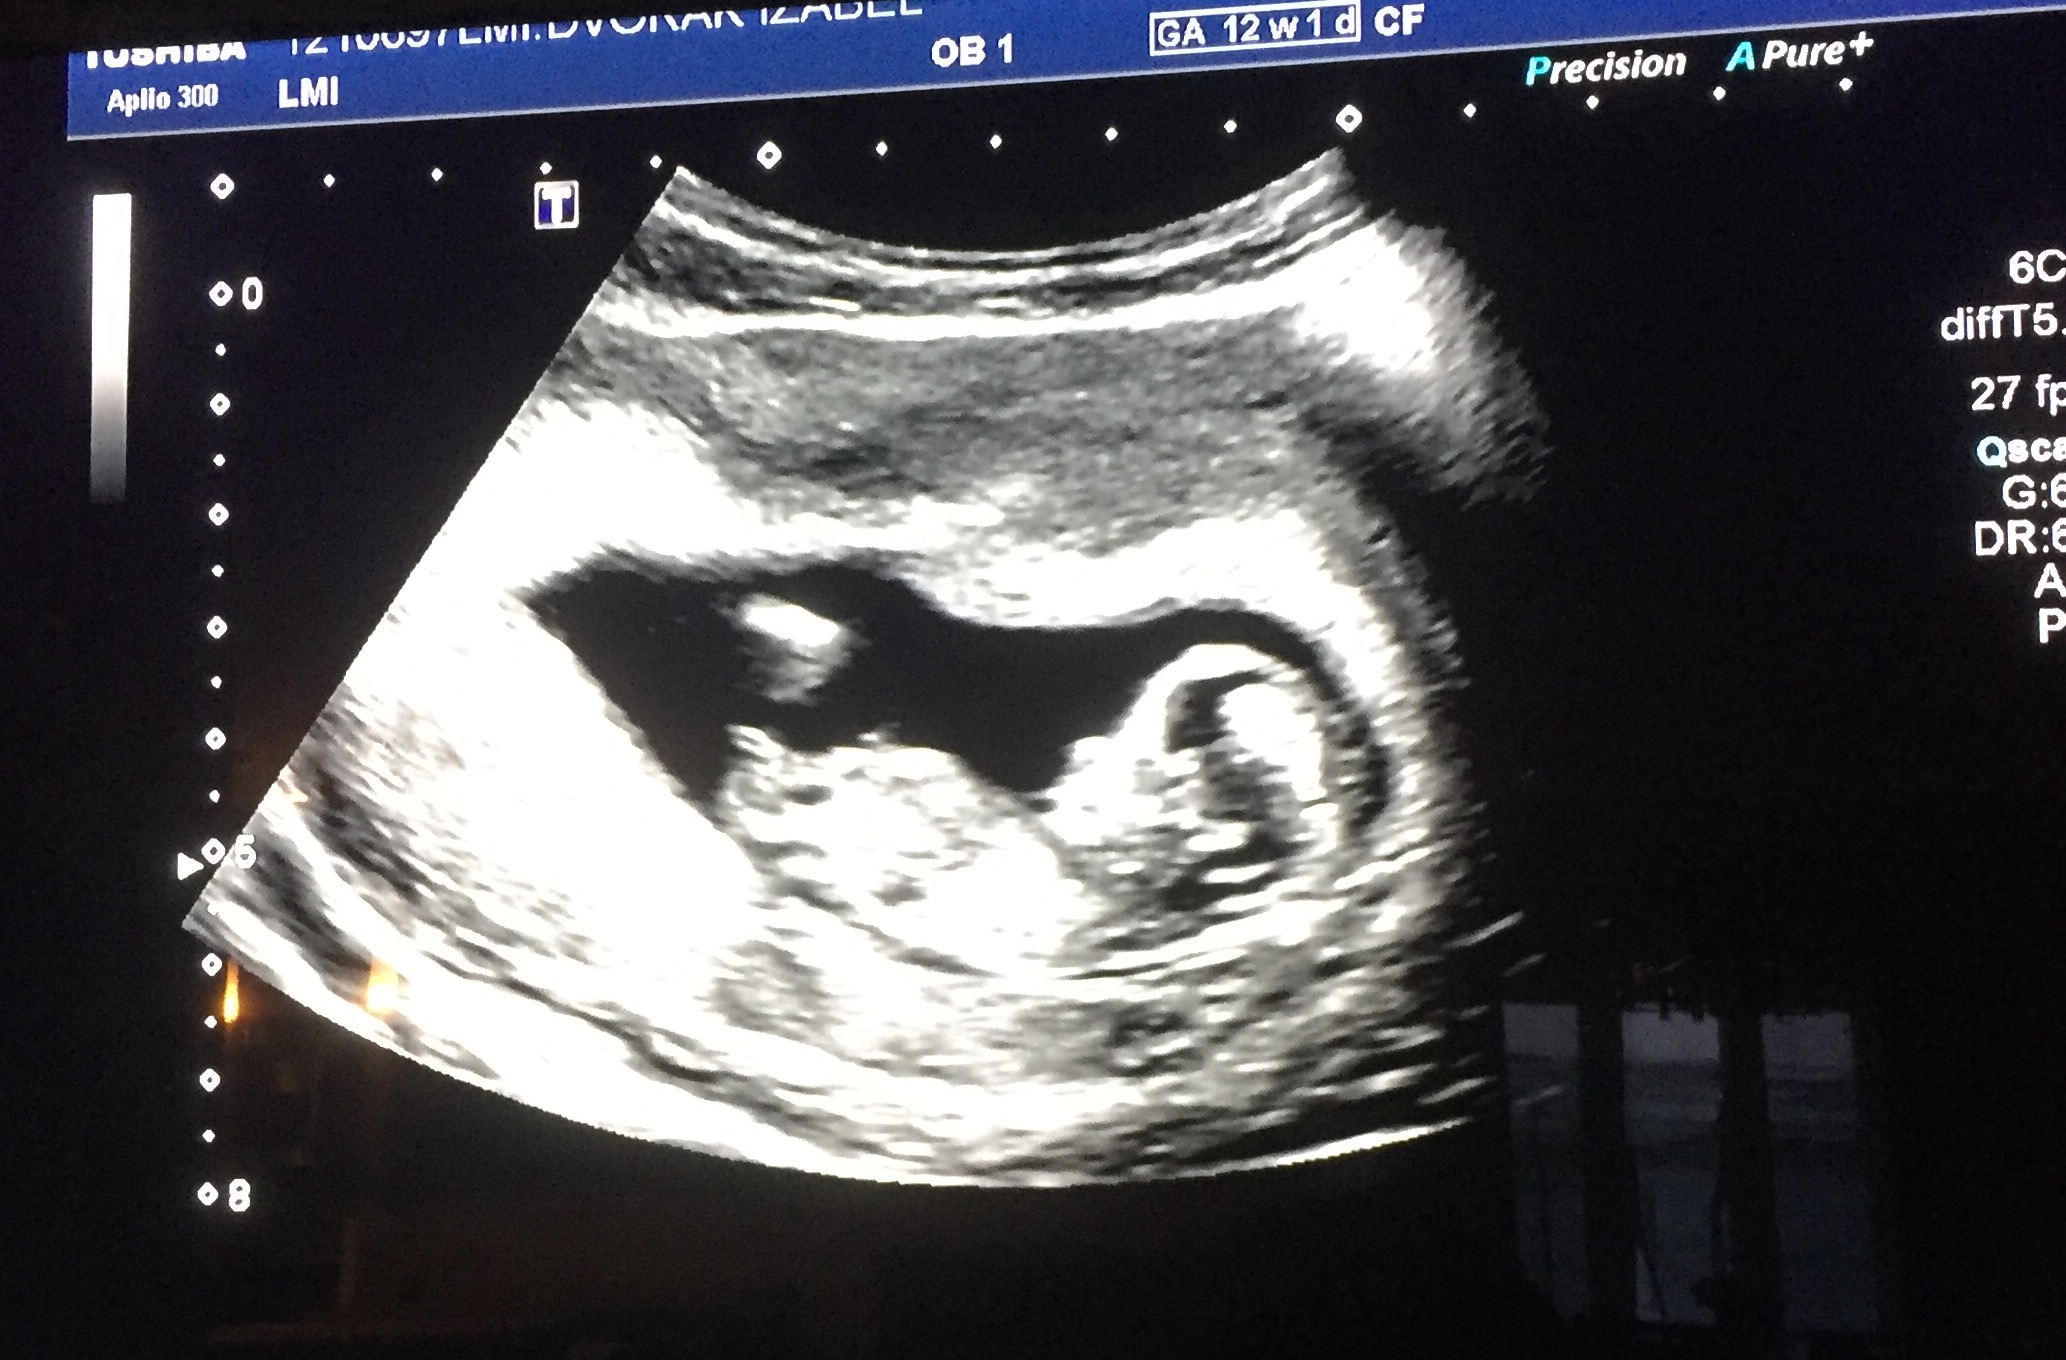

Biomedical papers of the medical faculty of the university palacky, olomouc, czech republic (2012) 5. 12 weeks 5 days ultrasound/ gender reveal. Will we find out the gender? While every woman is different, you may have several ultrasounds over the course of the first 20 weeks of pregnancy. 12 +5 week ultrasound nub guess. In case this is the first time you have heard about the nub the nub theory is a medical method used by professional healthcare physicians to get an early prediction of your baby's gender from an ultrasound. Gender confirmed by harmony test! While an ultrasound may predict gender as early as 12 weeks, dr. The nub theory cannot be used in the 11th week, but by the 12th and 13th weeks it's highly accurate. Ultrasound imaging performed in the 11th and 12th weeks of pregnancy for fetal gender identification identified the fetus either as a girl, a boy, or as a gender not assigned. frequency, sensitivity, specificity, positive and negative predictive values, and accuracy of the gender identification was. How to overcome gender disappointment. 100% of their if you want to learn your baby's gender, schedule your first trimester scan for 13 weeks gestation. I got a photo from the tech and i took some screenshots from a.

Some people however believe in nub theory, which suggests you can determine the gender of your baby from that first ultrasound photo by 12 week ultrasound gender. Nub theory is now helping expecting mothers and parents to find out about the gender of their child.